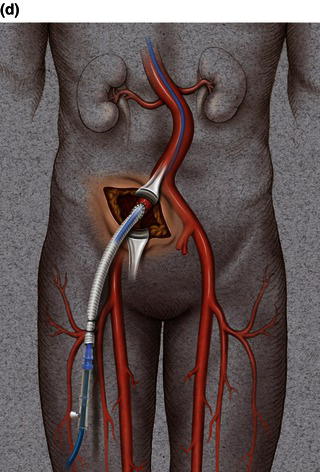

A 15 cm semi-lunar right flank incision is made four finger-breaths above the groin crease. Division of the external oblique, internal oblique and transversus abdominus muscles is performed in the direction of their fibers. The extraperitoneal fascia and peritoneum are then retracted medially and dissection is carried out in the avascular plane of the retroperitoneum down to the level of the psoas muscle. All of the abdominal contents are then retracted medially with the help of a handheld retractor or an Omni retractor, providing excellent exposure of the lower infrarenal aorta, common iliac artery, and iliac bifurcation. The right common iliac artery along with the hypogastric and the external iliac artery are identified and mobilized (Fig. 1.14a). Care is taken to spare the right urether which crosses the common iliac artery before diving deep into the pelvis. A Rummel tourniquet is applied to control the proximal common iliac artery, the external iliac artery, and origin of the hypogastric artery; alternatively, vascular clamps could be applied for control. Heparin is usually given to the patient prior to clamping the vessels. An arteriotomy is made on the common iliac artery with a no. 11 blade and extended with Pott’s scissors close to the bifurcation of the hypogastric artery and the external iliac artery. A 10 mm conduit is then sewn in an end-to-side fashion using 5-0 prolene sutures (Fig. 1.14b). The 10 mm graft is subsequently tunneled through the retroperitoneal space beneath the inguinal ligament and brought out through the groin incision used to expose the common femoral artery. The graft is subsequently flashed and clamped at the groin incision with the Rummel tourniquets released from the common iliac artery, external iliac artery, and hypogastric artery. The 10 mm conduit is subsequently looped with a Rummel tourniquet and ready to be punctured with an 18 gauge needle for access and introduction of a guide wire and an introducer sheath (Fig. 1.14c). The introducer sheath is subsequently exchanged for a device sheath, which is advanced into the distal aorta (Fig. 1.14d). The endoluminal graft is then introduced into the delivery sheath and deployed to the target area. Wires and sheaths are removed from the 10 mm conduit and the conduit is clamped.

The conduit can either be trimmed to the appropriate length and the conduit tied off as a stump (Fig. 1.14e) or the distal end of the conduit can be sewn to the more distal iliac system in an end-to-end fashion as an interposition graft. Or, more commonly, the conduit can be brought to the groin by tunneling the conduit under the inguinal ligament and performing either an end-to-end anastomosis or an ilio-femoral conduit. The ilio-femoral conduit is performed by making an arteriotomy on the adequately exposed common femoral artery after adequate proximal and distal control is achieved. An end-to-side anastomosis is constructed with a 5-0 prolene suture with adequate flushing maneuvers performed prior to completion of the anastomosis (Fig. 1.14f). The ilio-femoral conduit is best for patients who may require further intervention for diffuse thoracic aneurysmal disease as the conduit may be reused through a simple infrainguinal incision in the future. The groin incision is approximated in layers. The right flank incision is irrigated, a 10 Fr Jackson–Pratt drain is placed in the retroperitoneal space and the incision closed in layers. The same technique can be applied to the infrarenal aorta and thoracic aorta. Similarly, end-to-side grafting of a conduit to the axillary artery, as described elsewhere, to facilitate deep hypothermic circulatory arrest also provides excellent access to the thoracic aorta via the innominate [2].

Fig. 1.14 (a) Retroperitoneal exposure. (b) A 10 mm conduit sewn to the iliac artery. (c) Conduit brought out of the incision with cannulation of the conduit with an introducer sheath. (d) Introducer sheath exchanged for a device sheath and advanced through the 10 mm conduit to the distal abdominal aorta. (e) Ligation of a 10 mm conduit. (f) Conduit tunneled and sewn to the femoral artery as an ilio-femoral conduit.